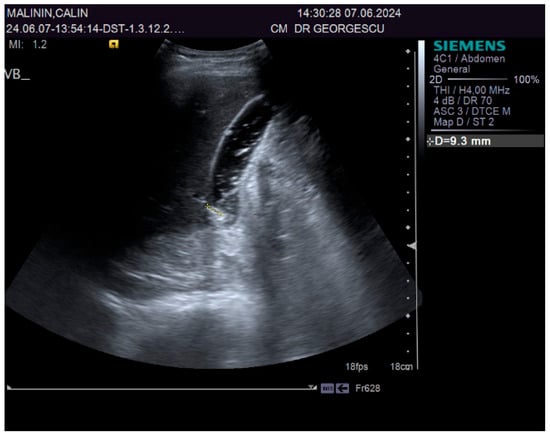

A 55-year-old male patient, complaining of recently onset, persistent generalized itching, was first examined by a dermatologist in the middle of May 2024 and no physical signs of skin disorder were found. Routine blood and stool workups were performed. No food or respiratory allergies were identified, and stool samples were negative for parasites. The recommended antihistamines were only partially effective, pruritus being present even during nights, resulting in a lowering of the patient’s quality of life. Given the mild dyspeptic-associated complaints, the patient was referred to a gastroenterological consultation on 7 June 2024 with a suspected biliary disorder. Medical history revealed no significant familial or personal pathologies, no smoking or alcohol drinking and no exposure to toxic substances. Physical examination found no particular pathological features, no peripheral palpable lymph nodes or skin lesions, normal respiratory and cardiovascular aspects, and blood pressure = 120/70 mmHg. However, the patient was overweight (BMI = 28 kg/m2) and displayed a mild palpatory tenderness of the middle and upper-right abdominal quadrant. Abdominal duplex ultrasound revealed multiple small echogenic formations adjacent to the gallbladder wall, likely cholesterol polyps. As illustrated in Figure 1 and Figure 2, two small calculi were also visualized in the infundibular zone. No biliary tree dilation was observed. Additional findings included mild liver steatosis, thickening of the stomach and duodenal walls, and a hyperechoic pancreatic texture. Aortic ectasia (2.7 cm in diameter) was noted just proximal to the distal bifurcation. No ascites or retroperitoneal lymph nodes were present.

Figure 1.

Ultrasound aspect: gallstones.